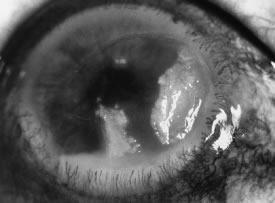

In the early stages of infection, filamentous fungi produce signs that are readily distinguishable from yeast or bacterial keratitis. The most distinctive sign is the presence of delicate, fine, feathery, opalescent, gray-white or yellow-white material in the anterior stroma, surrounded by scant cellular infiltrate or edema (Fig. 1). The epithelium may be intact. The overlying epithelium may be granular and the surface elevated and irregular in contour. Linear infiltrates typically extend into the adjacent stroma. Multiple discrete opacities may develop outside the perimeter of the principal focus of inflammation, either separated by clear stroma or linked by fine linear collections of inflammatory cells and material (Figs. 2 and 3). In the absence of inflammation in the adjacent stroma, branching hyphal fragments may be visualized by biomicroscopy (Figs. 4 and 5). Confocal microscopy may also detect hyphal elements within the stroma.28,29 Peripheral infection resembles noninfectious marginal infiltrative and ulcerative keratitis (Fig. 6). Multifocal keratitis may develop after contact lens wear or injury by multiple projectiles (Fig. 7). In the early stages, iritis is present and the intraocular pressure remains normal. Inappropriate, empirical therapy of fungal keratitis with topical fluoroquinolone or aminoglycoside antibiotics may suppress or eliminate the superficial elements but allow extension of the organisms into the stroma because these agents may possess selective antifungal activity.4,30,31

Fig. 1. Curvularia keratitis (slit-beam illumination). Note the fine feathery infiltrates extending from the central component, minimal cellular infiltrate in the adjacent stroma, and intact epithelium.